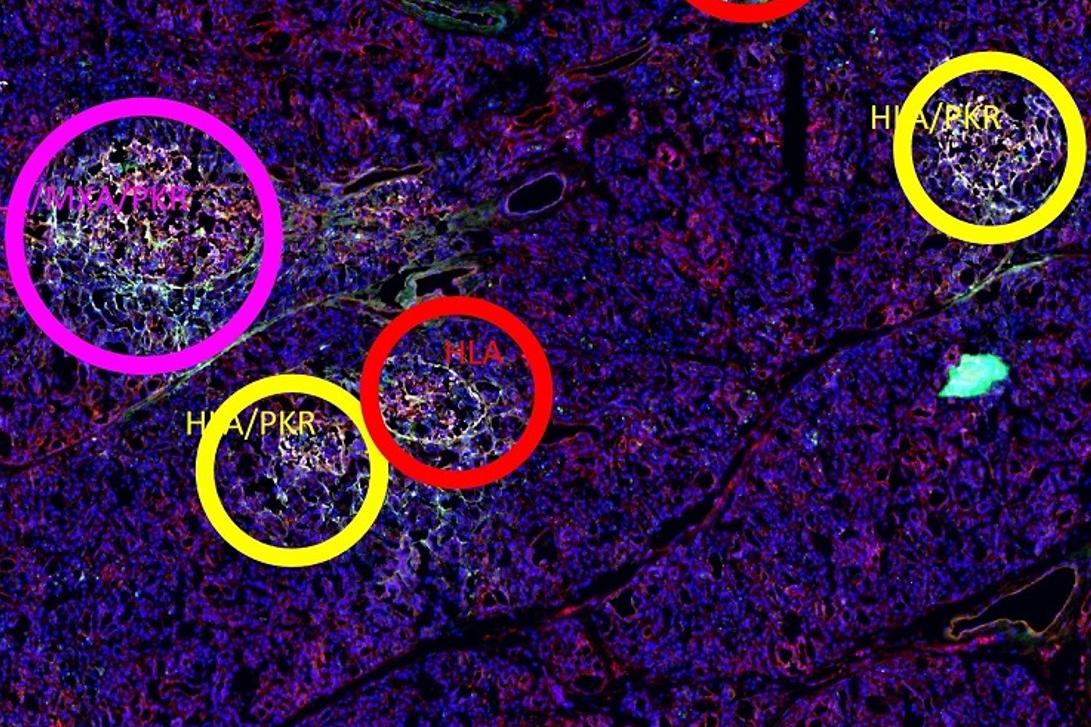

A whole pancreatic tissue section. Each positive islet was assigned a colored circle based on the number of expressed interferon response markers as follows: red for the expression of one marker, yellow for two markers, purple for three markers, and blue for four markers. Scale bar is 290 microns.

Upper inset of A whole pancreatic tissue section. Each positive islet was assigned a colored circle based on the number of expressed interferon response markers as follows: red for the expression of one marker, yellow for two markers, purple for three markers, and blue for four markers. Scale bar is 290 microns.

Middle inset of A whole pancreatic tissue section. Each positive islet was assigned a colored circle based on the number of expressed interferon response markers as follows: red for the expression of one marker, yellow for two markers, purple for three markers, and blue for four markers. Scale bar is 290 microns.

Lower inset of A whole pancreatic tissue section. Each positive islet was assigned a colored circle based on the number of expressed interferon response markers as follows: red for the expression of one marker, yellow for two markers, purple for three markers, and blue for four markers. Scale bar is 290 microns.